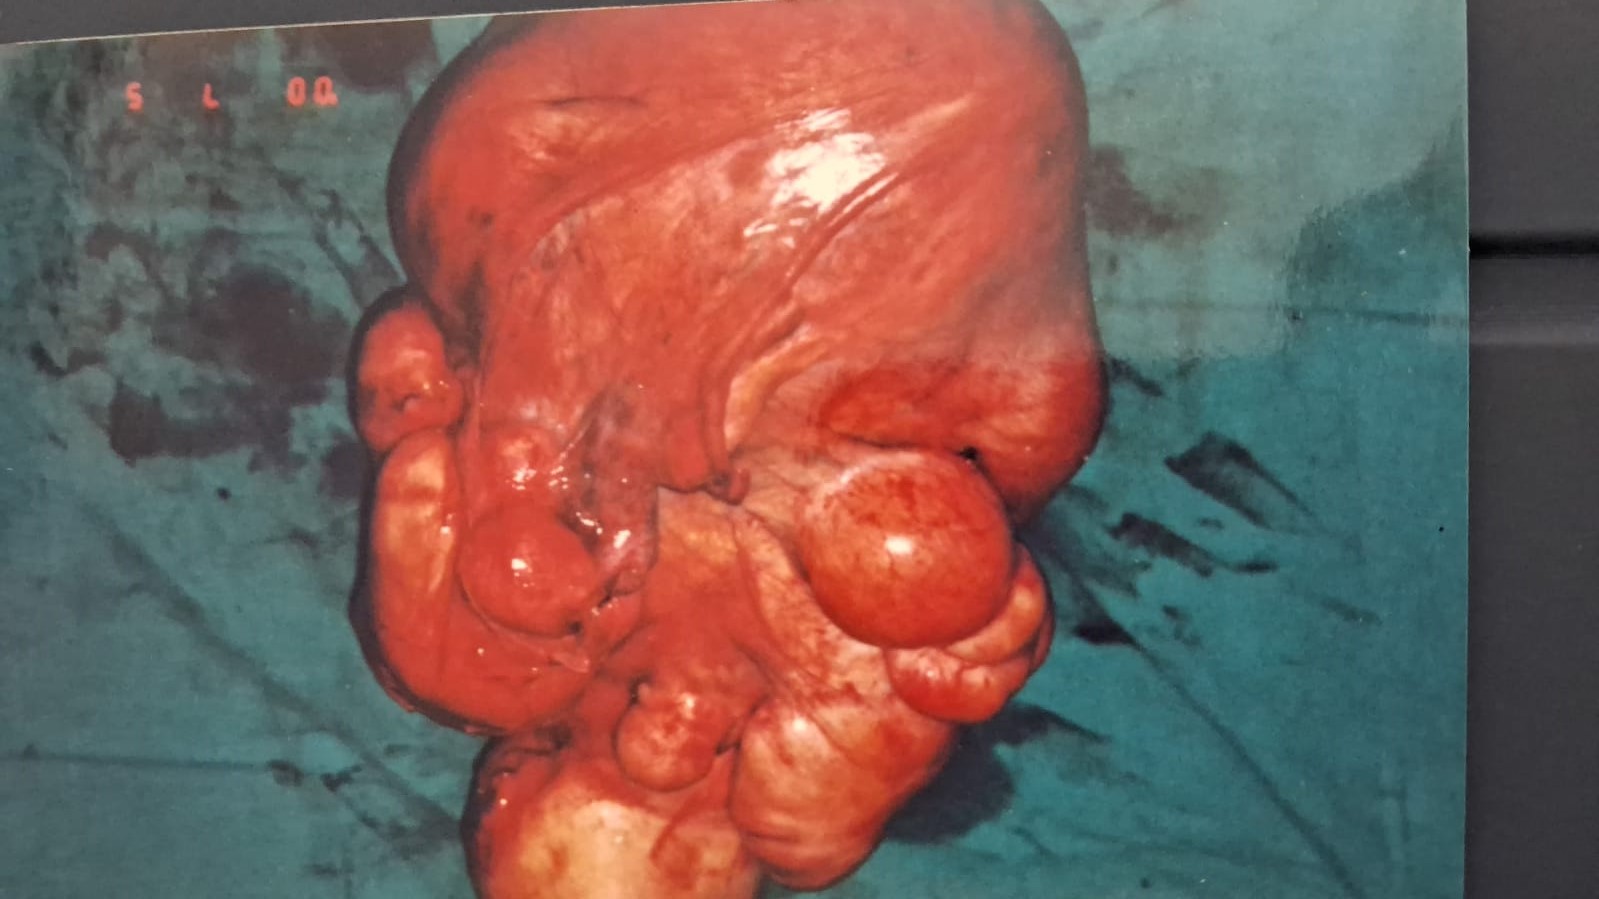

Multiple fibroid uterus